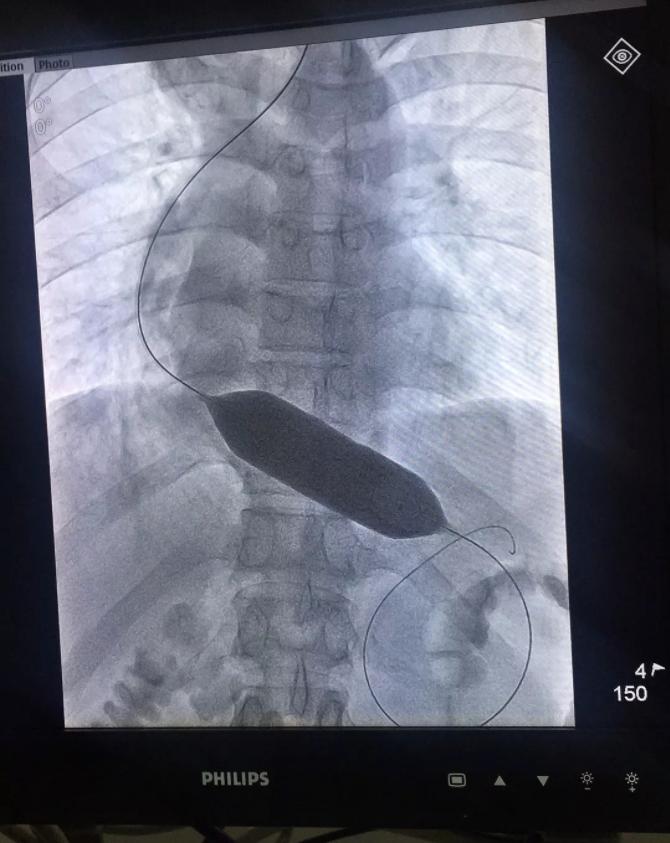

dsa下球囊扩张手术

对于这种失弛缓的治疗,对于轻度的我们一般通过饮食生活习惯的注意,其中包括一些药物治疗。药物一般都是松弛食管平滑肌的药,在吃饭之前10分钟-20分钟吃些药会好一些,这些药物包括硝苯地平、消心痛这类的。但对于中到重度的贲门失迟缓症,我们的治疗方案是介入下球囊扩张,首先贲门失弛缓就是贲门功能异常,在贲门一直收紧的状态下,食物咽不到胃里,还会造成严重反食、消瘦。长期下去造成食物潴留食管,食管扩张,短期并发症多影响生活质量,远期并发症致命。所以需要介入下球囊扩张解决问题,因为这种治疗手段远期疗效非常好,而且并发症非常少,它是通过球囊扩张让贲门的肌肉均匀的撕开,这样会大大减少术严重反流的出现率。